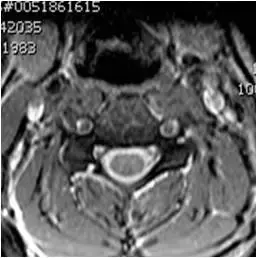

图38、轴向T2梯度回波图像。椎间盘突出与压迫硬膜囊。 轻度左钩椎关节肥大。

图39、轴向T2梯度回波图像。 左侧后外侧椎间盘突出伴压迫囊的前方。